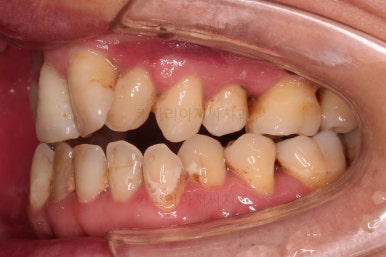

1. 초진 시 입안의 모습

부산구순구개열교정 키다리아저씨치과에 처음 내원하셨을 당시의 입안의 모습입니다.

이번 환자분도 이와 같은 일반적인 특징이 그대로 나타나 있었습니다.

양측성 구순구개열이었으므로 작은 앞니(대문니와 송곳니 사이)가 양쪽 다 결손이었고, 또 다른 이유로 아래 앞니도 1개 없는 상태였습니다.

초기 단계의 주안점은 아랫니와 악궁과 어울리는 윗니 악궁의 형태를 만들어 주는 것이고요.

악궁확장장치를 사용하지 않은만큼 철사의 형태를 잘 잡아가면서 악궁 형태를 개선시킵니다.

교정 10개월째인데, 악궁형태 많이 좋아졌고, 가지런한 느낌도 많이 좋아졌습니다.